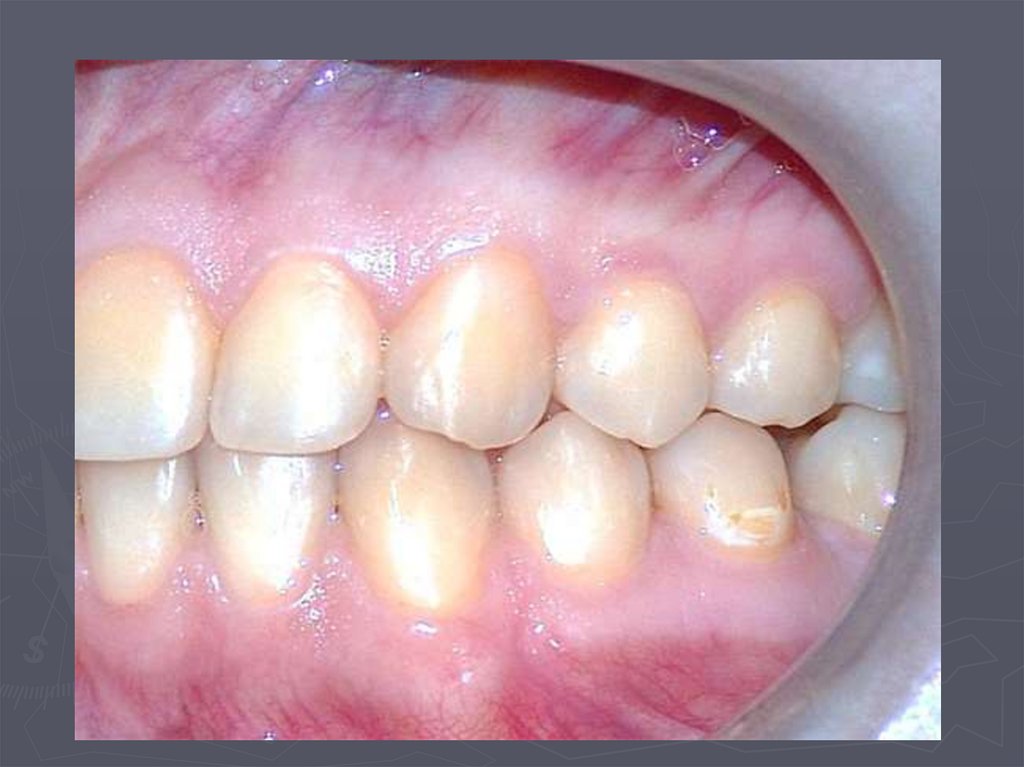

16. При компенсированной форме кариеса:

► отмечается высокая устойчивость тканей зубов к

кариесу;

► индекс кп, КПУ, кп +КПУ не более 3;

► поражаются преимущественно моляры;

► кариозные полости локализуются преимущественно на

жевательной поверхности;

► осложненный кариес развивается редко;

► удаленные зубы отсутствуют;

► редко наблюдается выпадение пломб, развитие

вторичного кариеса, переход неосложненной формы в

осложненный;

► прирост кариеса невысокий.

Компенсированная форма кариеса встречается у

детей здоровых, практически здоровых;